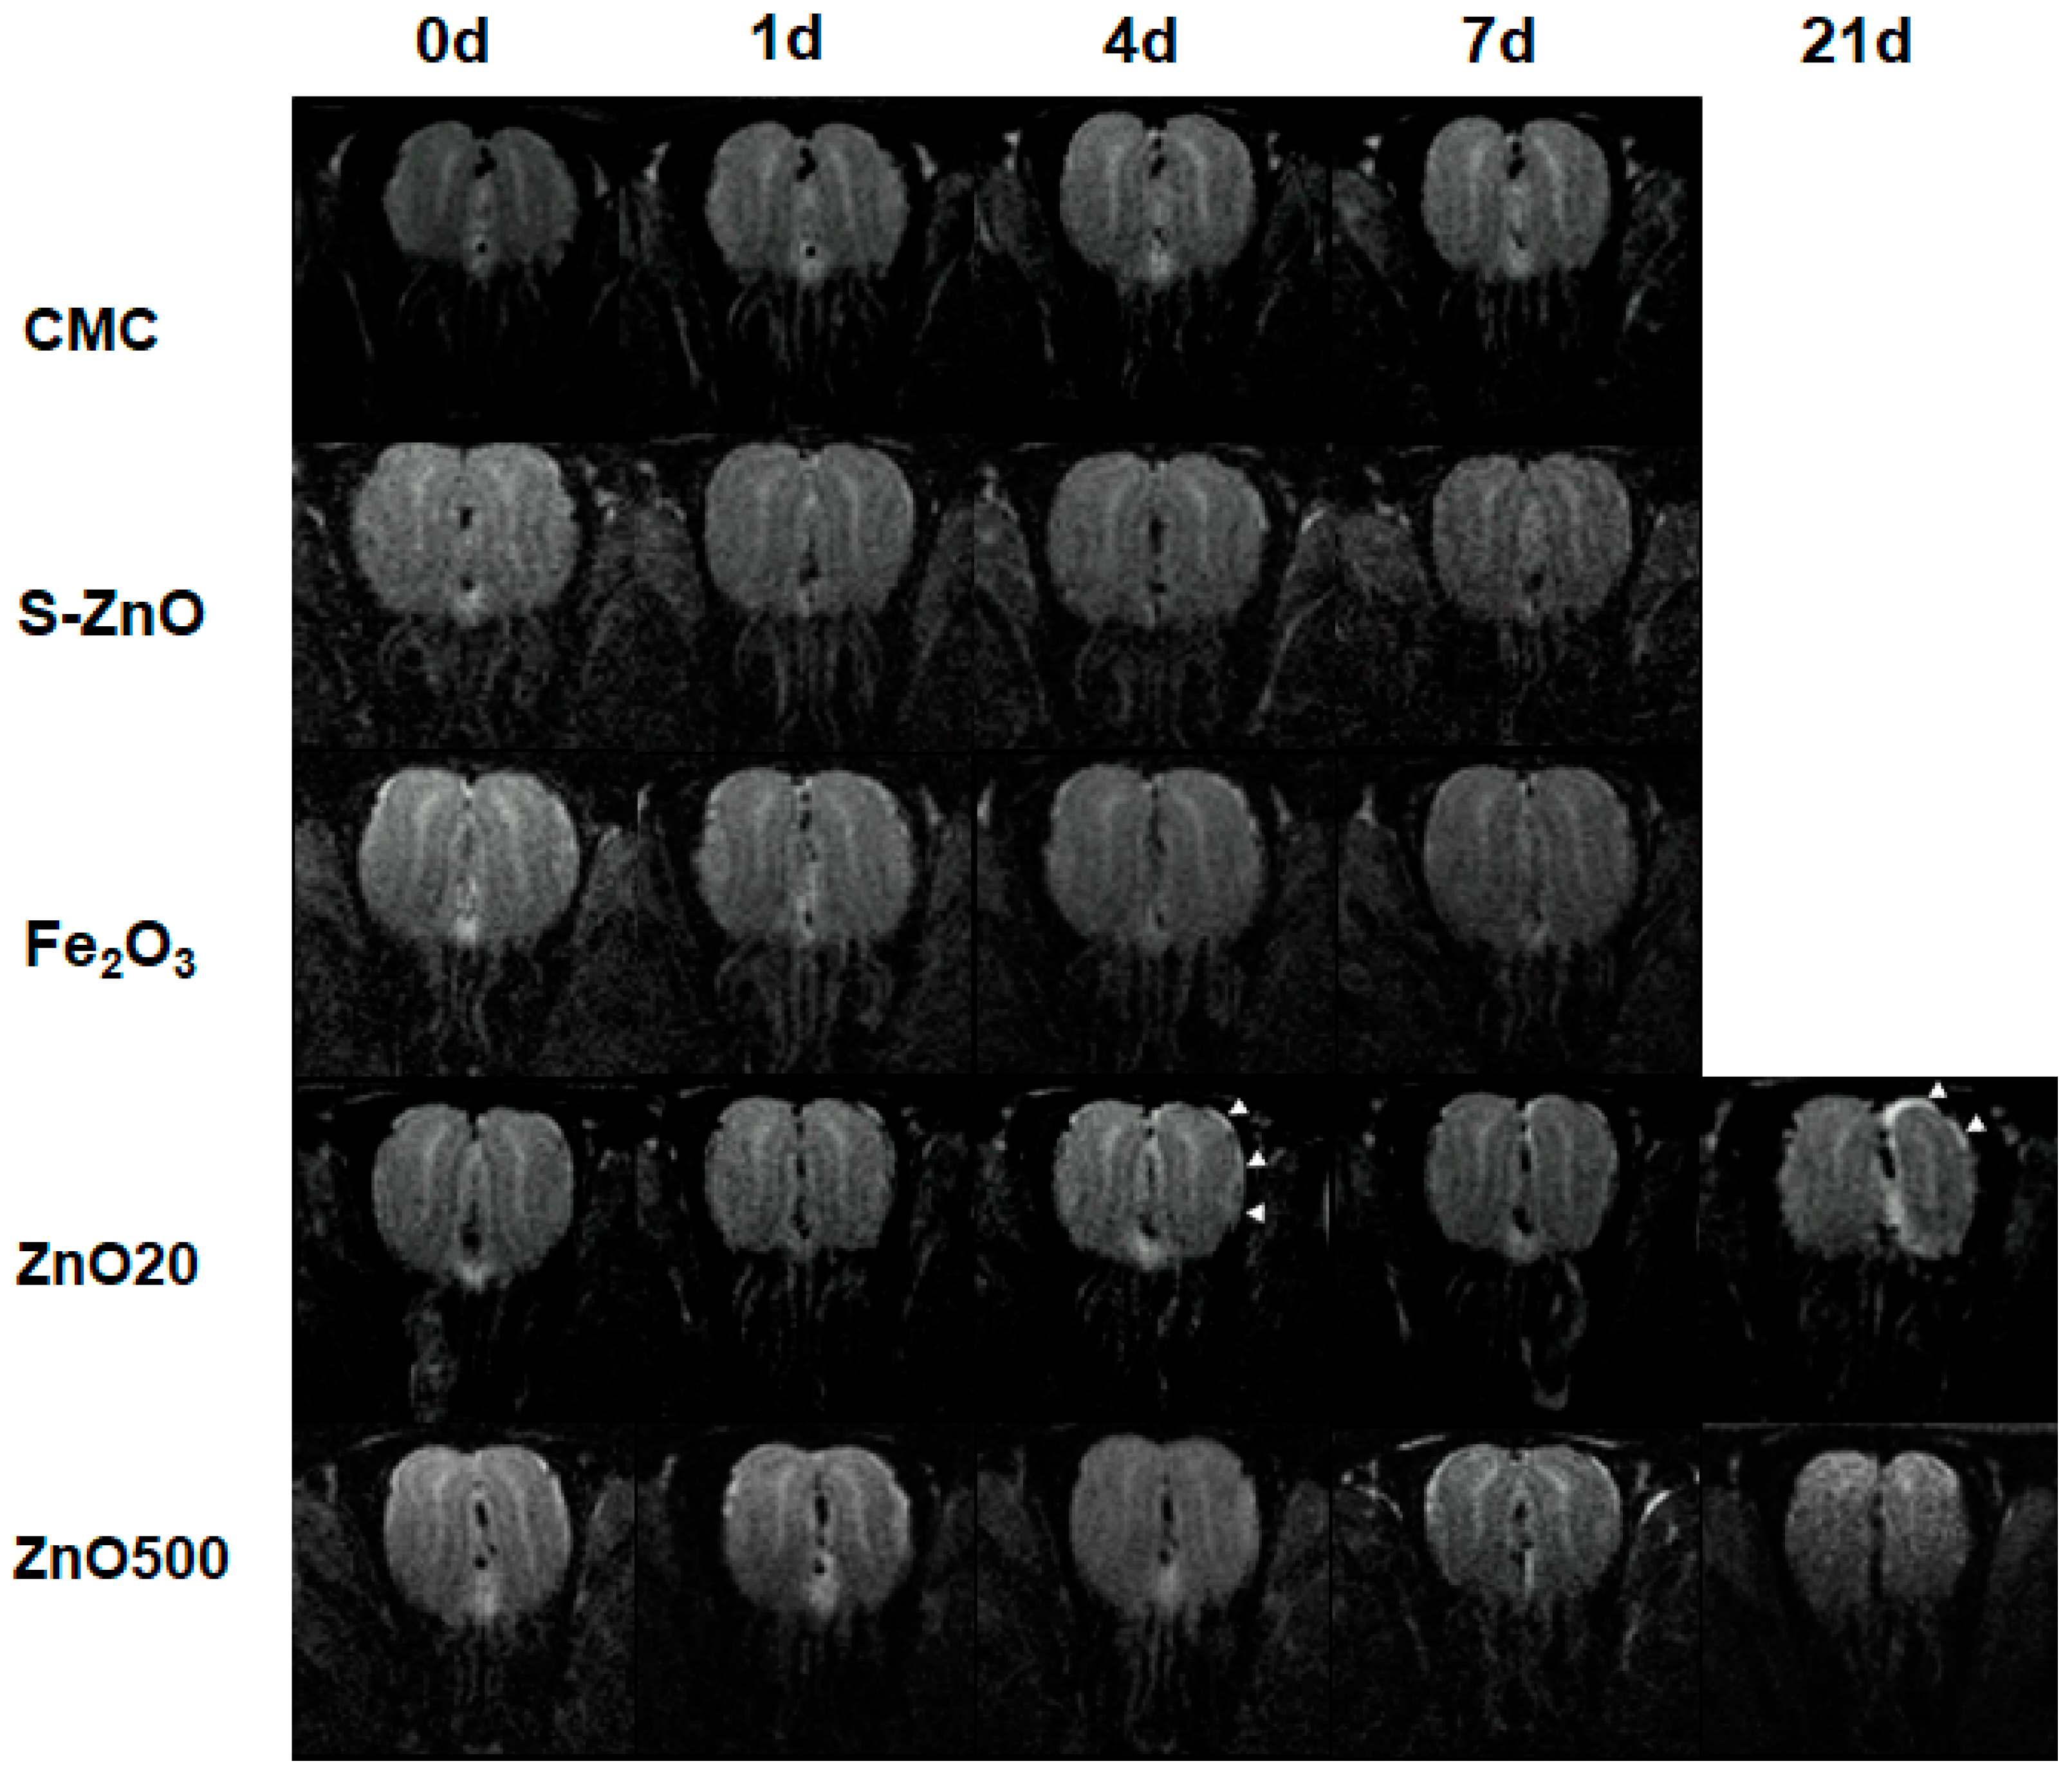

3.2. Toxic Effects of 20-nm ZnO NPs

3.3. Structural Changes of the OE and OB